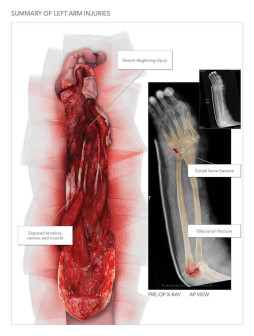

Left Shoulder and Arm Injury

Available in high resolution JPEG or PDF formats, 8x10 print, or laminated foam core exhibit board (24x46, 30x40 or 36x48).